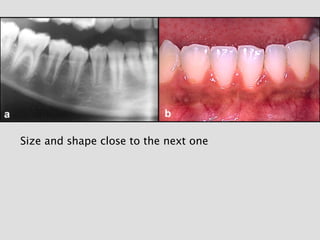

Supernumerary teeth can be classified by shape and by

Size and shape close to the next one